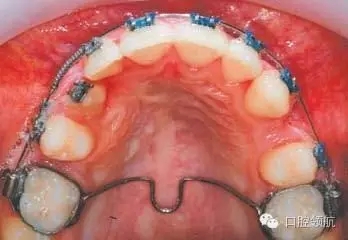

圖3.10中使用的矯治方法是什么?

在0.018英寸的不銹鋼圓絲上使用鎳鈦推簧為排齊UR3開拓間隙。在其作用下UR4遠中移動,而UR2近中移動協(xié)助糾正中線不齊。使用彈性牽引力將UR3向遠中、頰側(cè)移動,同時使用橫腭桿加強磨牙支抗。需要注意的是使用推簧開拓間隙時,應(yīng)保證UR2、UR4被動結(jié)扎于主弓絲上以防止扭轉(zhuǎn)。

為什么在此治療階段應(yīng)該選擇0.018英寸不銹鋼圓絲作為主弓絲?

首先,不銹鋼絲具有足夠的硬度,可以為彈性牽引提供支抗并防止其副反應(yīng)的發(fā)生(如牙弓變形等)。其次,圓絲可以降低滑動摩擦力,從而有利于牙齒移動。